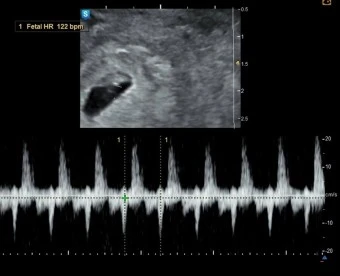

의사 선생님은 임신 7주 2일 차라고 말씀하시면서 아기집을 보여주셨다.

아기집은 2주 전 보다 많이 커졌고 그 안엔 비비탄만 한 아기도 보였다.

종연이 쪼끄만 게 아기집에 야무지게 꼭 붙어 있는 모습이 너무 귀엽다고 느낀 순간 리듬감 있고 묵직한 소리가 종연의 마음을 뭉클하게 두드렸다.

두둥~두둥~두둥~

종연과 손임은 진료실 전체가 울릴 만큼 엄청 큰 아기의 심장소리를 넋을 잃고 듣고 있었다.

의사 선생님께서는 종연과 손임 부부가 충분하다고 느낄 만큼 시간을 들여 아기의 심장소리를 들려주셨다.

“여기 깜빡깜빡하는 거 보이시죠? 아기가 심장박동 할 때마다 깜빡거리는 거랍니다.’

종연은 비비탄 크기의 아기 속에 심장이 있다는 것과 이토록 우렁차고 빠르며, 쉬지 않고 뛰고 있다는 사실에 경이롭기만 했다.

“아기집, 아기 모두 정상적인 범주에서 수주만큼 잘 자라고 있어요. 심장소리 크기랑 속도, 패턴도 정상입니다.”